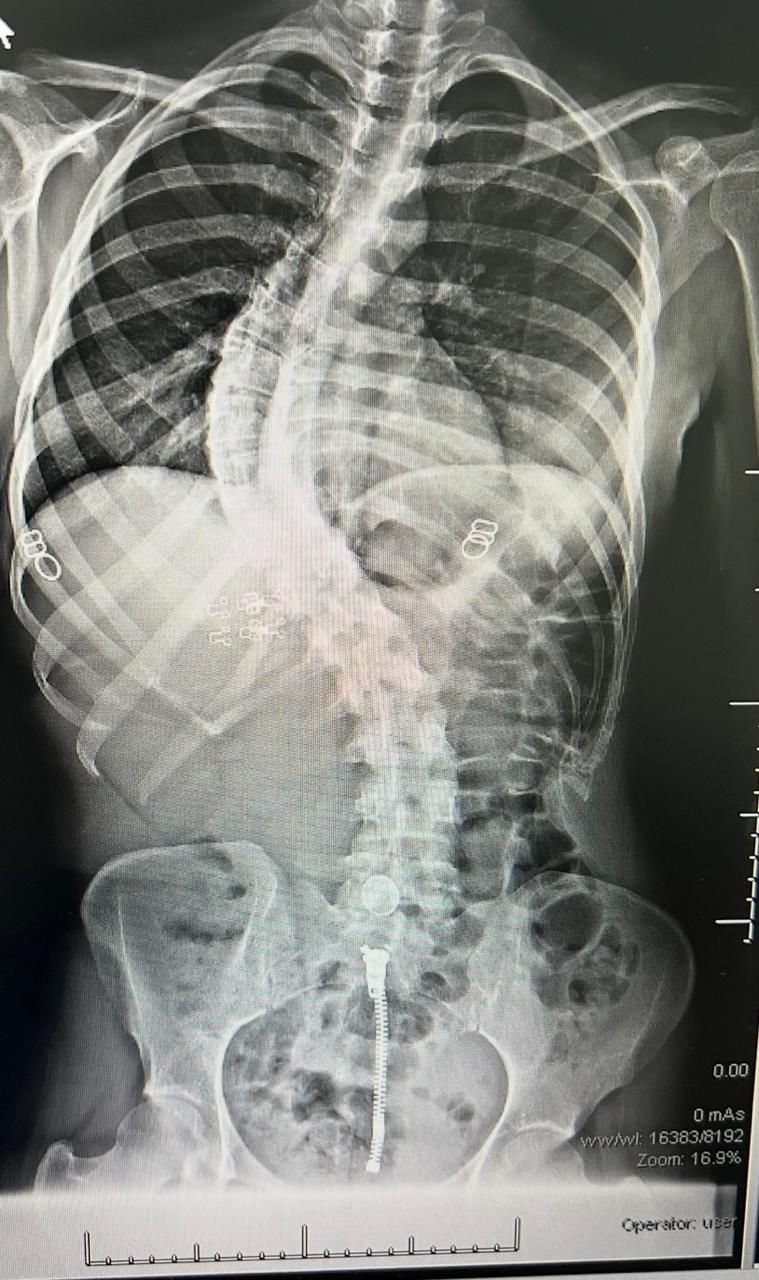

وجرى تشخيص الحالتين بعد تقييم طبي دقيق شمل الفحوصات الإكلينيكية والأشعة اللازمة، حيث تبين وجود درجات متقدمة من انحناء العمود الفقري استدعت التدخل الجراحي. وتم تنفيذ العمليتين باستخدام أحدث التقنيات الطبية، مع الاعتماد على أجهزة المراقبة العصبية لضمان أعلى مستويات الأمان أثناء الجراحة.

وتعد هذه العمليات من الإجراءات الجراحية الدقيقة والمعقدة، إذ تتطلب تنسيقا عاليا بين الفريق الجراحي والتخدير، إضافة إلى مراقبة عصبية مستمرة، وقد استغرقت كل عملية نحو ثمان ساعات.